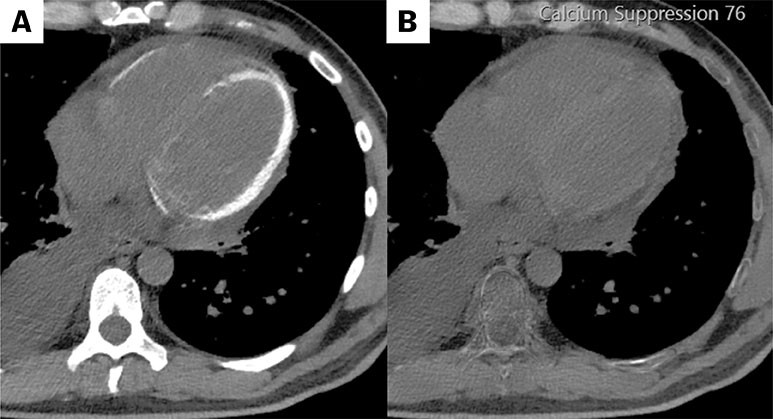

The CT images are from a scan without intravenous contrast. The image on the left shows high attenuation in the left ventricular myocardium, and to a lesser extent in the right ventricle. The attenuation closely resembles the appearance of bone in the image, and the density can be consistent with calcification.

The image was taken using spectral CT, which offers superior tissue differentiation. The machine utilises X-ray photon energy spectra, allowing it to differentiate between chemical elements like iodine and calcium based on their absorption levels, as both produce high attenuation. Calcium suppression, shown in the image on the right (B), confirms that the high attenuation in image (A) is due to the presence of calcium in the tissue.

The images are of a man in his 40s with diet-controlled diabetes and no known chronic kidney or heart disease. Four weeks prior to the images being taken, he was admitted to hospital with E. coli sepsis, which resulted in multiple organ failure and intensive care with haemodialysis. The indication for chest CT was significant pleural effusion, and the finding of myocardial calcification was unexpected. Three weeks later, echocardiography showed substantially increased myocardial echogenicity, except in the septum (see video online). The myocardium was contracting, but the ejection fraction was reduced by an estimated 40 %, primarily longitudinally.

The CT and echocardiography findings are consistent with diffuse myocardial calcification. This condition has been described in some case reports and can occur due to a disturbance in the calcium and phosphorus balance, chronic renal failure, or, as in this case, inflammatory damage to the myocardium following sepsis with kidney failure (1). The condition increases the risk of heart failure, and monitoring of the heart function is indicated (2). There is currently no targeted therapy for reducing calcification, but spontaneous regression was observed in another case report (3).